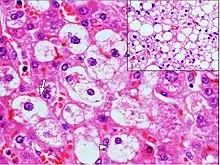

| Micrograph demonstrating marked (macrovesicular) steatosis in non-alcoholic fatty liver disease. Masson's trichrome stain. | |

Steatosis reflects an impairment of the normal processes of synthesis and elimination of triglyceride fat. Excess lipid accumulates in vesicles that displace the cytoplasm. When the vesicles are large enough to distort the nucleus, the condition is known as macrovesicular steatosis; otherwise, the condition is known as microvesicular steatosis. While not particularly detrimental to the cell in mild cases, large accumulations can disrupt cell constituents, and in severe cases the cell may even burst.

Histology

Histologically, steatosis is physically apparent as lipid within membrane bound liposomes of parenchymal cells.[2] When this tissue is fixed and stained to be better viewed under a microscope, the lipid is usually dissolved by the solvents used to prepare the sample. As such, samples prepared this way will appear to have empty holes (or vacuoles) within the cells where the lipid has been cleared. Special lipid stains, such as Sudan stains and osmium tetroxide are able to retain and show up lipid droplets, hence more conclusively indicating the presence of lipids. Other intracellular accumulations, such as water or glycogen, can also appear as clear vacuoles, therefore it becomes necessary to use stains to better determine what substance is accumulating.

Histological section of a mouse's liver showing severe steatosis. The clear vacuoles contained lipid in life; however, histological fixation caused it to be dissolved and hence only empty/clear spaces are seen.

Micrograph of fatty liver showing lipid steatosis. H&E stain.

Steatosis with a centrilobular pattern, which is the general tendency for steatosis in adults.[11]